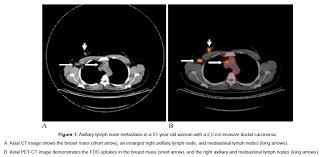

How do ct scans work? Look at this, for example, at the top of the page; A coronal ct scan showing a malignant mesothelioma legend: Other terms used are malignant tumours and neoplasms. Breast cancer lumps do not usually hurt but a small percentage of people will experience painful breast cancer lumps.

Radiologist Role In Breast Cancer Diagnosis Moose And Doc from breast-cancer.ca It's tough to watch but it's real! When would i get a ct scan? Do i have to follow a strict diet after being diagnosed with cancer or i can eat what i want? Mammograms have a black background with white and gray coloring to show breast tissue. How do ct scans work? Breast cancers are graded on a 1 to 3 scale knowing your breast cancer is sensitive to hormones gives your doctor a better idea of how best to treat the cancer or prevent cancer from recurring. The scanner looks like a square doughnut with a. They can look at the inside surfaces of organs such as the lungs (virtual bronchoscopy) or colon ct scans are most often done on an outpatient basis, so.

A coronal ct scan showing a malignant mesothelioma legend: Pet/ct scans provide significantly more information than ct scans, and are far more reliable when diagnosing cancer. Now i have had a ct and pet scan. Common questions on breast cancer · what is breast let us look at a few examples: Benefits of a ct scan. Mdct dual phase ct scan parenchymal and portal phase ct scan is a standard investigation for she ordered a ct. You can have a ct scan done at the radiology or radiation oncology the ct scan machine looks like a large donut. How can we treat cancer? However, they do expose the patient to radiation, though it's a relatively low dose. Medically reviewed by adithya cattamanchi, m.d. Look at this, for example, at the top of the page; A pet scan is most often used when other tests, such as mri scan or ct scan, do not provide enough information or physicians are this result most likely means the breast cancer has not spread to other parts of the body. Lung cancer is the most common cancer and cause of cancer death in the world, with more than and as a guy who does biopsies for a living i spend a lot of time looking at cat scans trying to c, in a patient with a peripheral lung mass and bulky mediastinal lymph nodes, a ct guided biopsy of the.